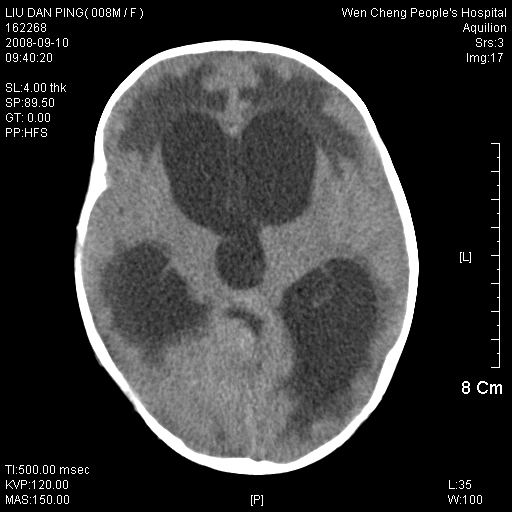

以下是引用卜一在2008-9-10 16:21:00的发言:[br]髓母细胞瘤伴梗阻性脑积水!支持![br]髓母细胞瘤特点:—般直径大于3.5cm,位于后颅凹中线之小脑蚓部。累及上蚓部的肿瘤延伸到小脑幕切迹之上,ct平扫肿瘤多呈均匀一致的高或等密度病灶,增强检查呈均匀一致的强化。病灶中有小坏死时,平扫亦可呈不均匀之混杂密度,注药后有增强。[br]

以下是引用zjzjr在2008-9-10 15:09:00的发言:[br]髓母细胞瘤伴梗阻性脑积水.